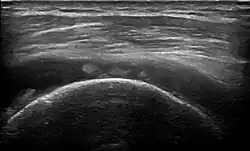

Sonographie

Die Sonographie gilt als Methode zur Erstuntersuchung, da es sich um eine kostengünstige und weithin verfügbare Technik handelt.[11] Eine Metaanalyse ergab für die Detektion (Nachweis) partieller Risse eine Sensitivität (Trefferquote) von 67 % und eine Spezifität von 94 %; für komplette Risse bestand eine Sensitivität von 92 % und eine Spezifität von ebenfalls 94 %.[12]

Ultraschall kann sowohl den Riss direkt als echoarme Region oder Fehlen von Sehnenfasern darstellen als auch indirekte Zeichen abbilden, die auf einen Sehnenriss hinweisen: Zu Letzteren gehören eine Abflachung der Sehne, unregelmäßige Oberfläche der Knochenvorsprünge (Tuberculi) am Oberarmknochen und eine echogene Linie entlang des Knorpels (cartilage interface sign). Auch ein Erguss im Schultergelenk, im Schleimbeutel Bursa subacromialis-subdeltoidea unterhalb des Grätenecks am Schulterblatt und des Deltamuskels sowie in der Sehnenscheide des Bizeps legen den Verdacht einer Rotatorenmanschettenruptur nahe.[13]